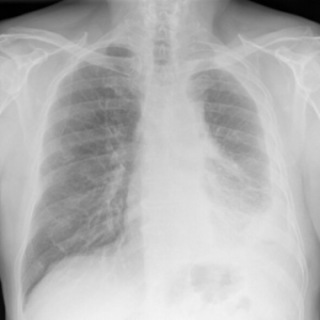

Mesothelioma X-Ray Scans

X-rays are mesothelioma imaging scans that offer a fast, low-dose way to look for problems in the chest. Doctors use them to spot fluid around the lungs, areas of unusual thickening or a collapsed lung that may signal pleural disease.

Doctors check for warning signs linked to mesothelioma, like pleural effusion, pleural thickening, or a partly collapsed lung. X-rays can miss small or early tumors, and they do not diagnose cancer alone. If your X-ray raises concern, your doctor will order advanced scans and, if needed, a biopsy to be sure.